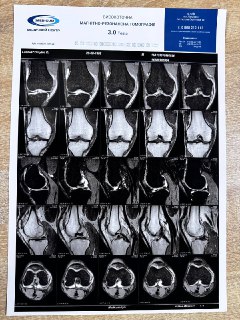

Тільки отримав МРТ. На щастя нічого серйозного. Реактивне подразнення капсули, меніскова іритація заднього рога. Ще бачу запалення мʼяких тканин.

З лівим коліном у мене все набагато гірше, але такий пекельний біль-це дещо. Тому реабілітація буде максимум місяць. Всі кроки буду записувати як відео тренування і викладати. Як добре що у мене є я і що стільки часу та грошей витратив на навчання